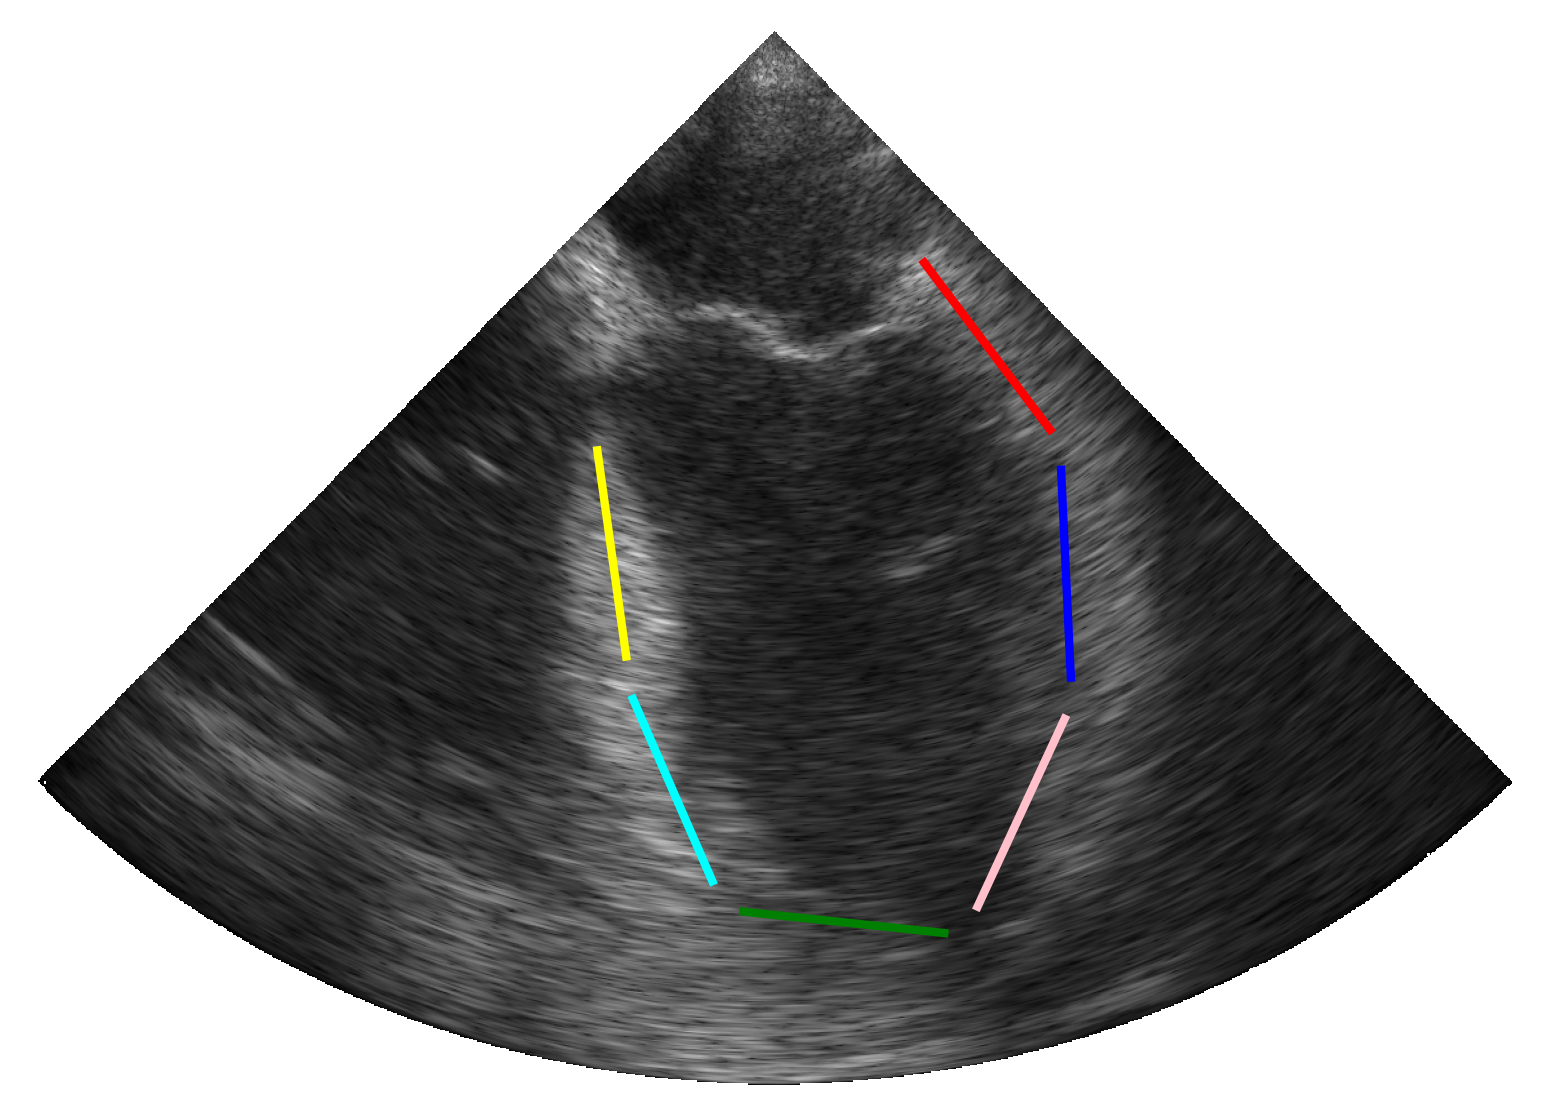

2.3.2 Simulation of Synthetic Infarction

To account for patients with hypokinetic pathologies, we enhanced the simulation pipeline by designing additional scenarios that simulate myocardial infarction in one of the six cardiac segments. Based on the pipeline described above (c.f. Figure 1), a synthetic myocardial motion was first estimated from a real sequence using the same technique as previously described [14]. The longitudinal contraction of myocardial scatterers was then reduced locally (i.e. at the center of a specific segment) following a Gaussian distribution throughout the cardiac cycle. The scatterers in the surrounding tissues were finally designed to compensate for the reduced contractility in order to maintain overall contraction, thus enabling the rest of the pipeline to be preserved.

3.1.3 Local Deformation Abnormalities

We extended our pipeline to simulate myocardial infarction, aiming to assess our model’s ability to detect and adapt to localized hypokinetic dysfunction in cardiac muscle. This was done through an ablation study whose results were given in Table 4. Using the combined strategy, we trained our TeeTracker on the fourth dataset described in Table 1, with and without a fifth dataset involving synthetic infarction. The model trained on the dataset incorporating synthetic infarction demonstrated remarkable generalization to regional variations in myocardial contraction, with a mean distance error of 0.37 0.06 mm across all segments and 0.36 0.11 mm on infarcted segments. Moreover, this model outperformed the one trained without synthetic infarction, which achieved a mean distance error of 0.58 0.14 mm across all segments. These results also hold for the clinical metrics, where TeeTracker trained on the combined dataset with synthetic infarcts achieved the best scores with a mean difference (95% limits of agreement) of 0.14% (-2.60% to 2.88%) for SLS and a mean difference (95% limits of agreement) of 0.11% (-0.69% to 0.91%) for GLS. The quality of these results was further validated through the Bland-Altman plots provided in Figure 4. Finally, Figure 5 shows the reference and segmental strain curves estimated by our TeeTracker models from a simulated sequence with an infarct region. Visual inspection of the curves reveals that our best model successfully identified and localized the infarcted segments, maintaining a coherent global contraction pattern while accurately reflecting regional dysfunction. These results demonstrate the ability of TeeTracker to detect and quantify myocardial abnormalities, thereby enhancing its clinical applicability for real-world TEE data.